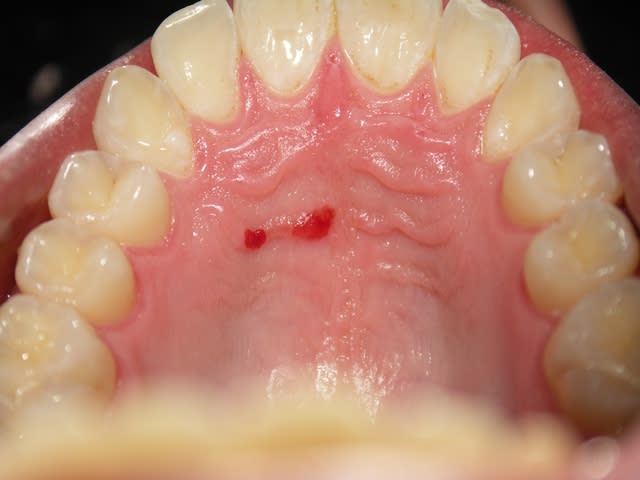

Besoin d'un avis sur cette lésion au palais d'un patient de 25 ans , sans problèmes de santé.

En passant le dos de la sonde dessus, pas de décoloration ni de reliefs , absence de douleurs .

Le patient n'avait pas connaissance de cette lésion à cet endroit.

Fumeur depuis 6/7 ans , 15 cigarettes par jour.

on dirait de petits angiomes..

idem, petits angiomes je pense

Faut attendre 1 semaine pour moi c'est juste une blessure.

Angiome=> Disparait a la pression

Kaposi => Disparait PAS a la pression.

Tumeur maligne => Ca n'a pas vraiment la gueule. Quoi que...

Purpura/petechie => Tres tres peu probable.

Oh ben, les erythroplasies sont fréquemment associées au carcinome epidermoide.

Est ce qu'il y a un aspect "velouté" ? On dirait que non

Le plus probable reste la blessure qui va disparaître sous peu.